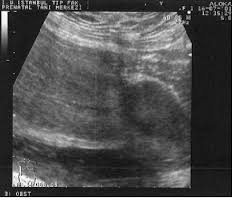

Ultrasound Video Showing Inflammatory Fluid In Culde-Sac.

Ultrasound Video Showing Inflammatory Fluid In The Cul-De-Sac And A Hemorrhagic Ovarian Cyst.